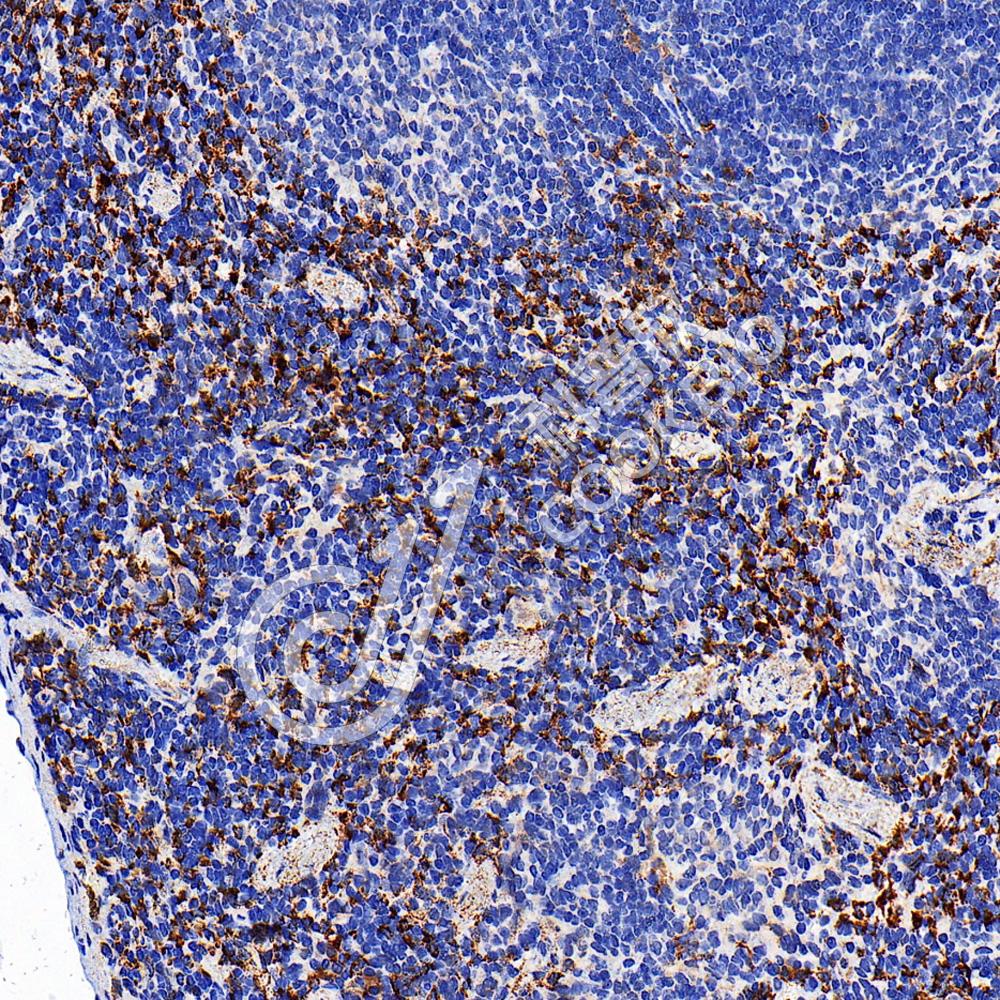

IHC检测Mannose Receptor/CD206蛋白(货号 K5460491).

样品: 小鼠脾, 4%多聚甲醛 (货号KSG1101) 固定12-24小时.

抗原修复: Tris-EDTA抗原修复液(pH 9.0) (货号KSG1203), 水浴100℃, 25分钟.

—抗: 1: 2000稀释, 4℃ 孵育过夜.

二抗: S-vision免疫组化多聚二抗(山羊抗兔),即用型 (货号KB3906), 室温孵育20分钟.